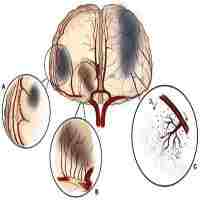

| Abstract | Symptomatic intracranial atherosclerotic disease (sICAD) remains a challenging disorder in the neurovascular field. Despite best medical treatment (BMT), the recurrence rate for stroke remains high in patients with intracranial high-grade stenosis (>70-99%). Furthermore, two large randomized trials (SAMMPRIS and VISSIT) failed to prove the efficacy of percutaneous transluminal angioplasty and stenting (PTAS) in patients with sICAD. Drug-coated balloon percutaneous transluminal angioplasty (DCB-PTA) represents an alternative treatment modality with therapeutic benefits for interventional cardiology. However, there are very few articles in the existing literature that relate to the use of DCB-PTA in sICAD patients. Here, we aimed to review the rationale underlying the use of DCB-PTA in sICAD patients and summarize recent developments in the neurovascular field. |